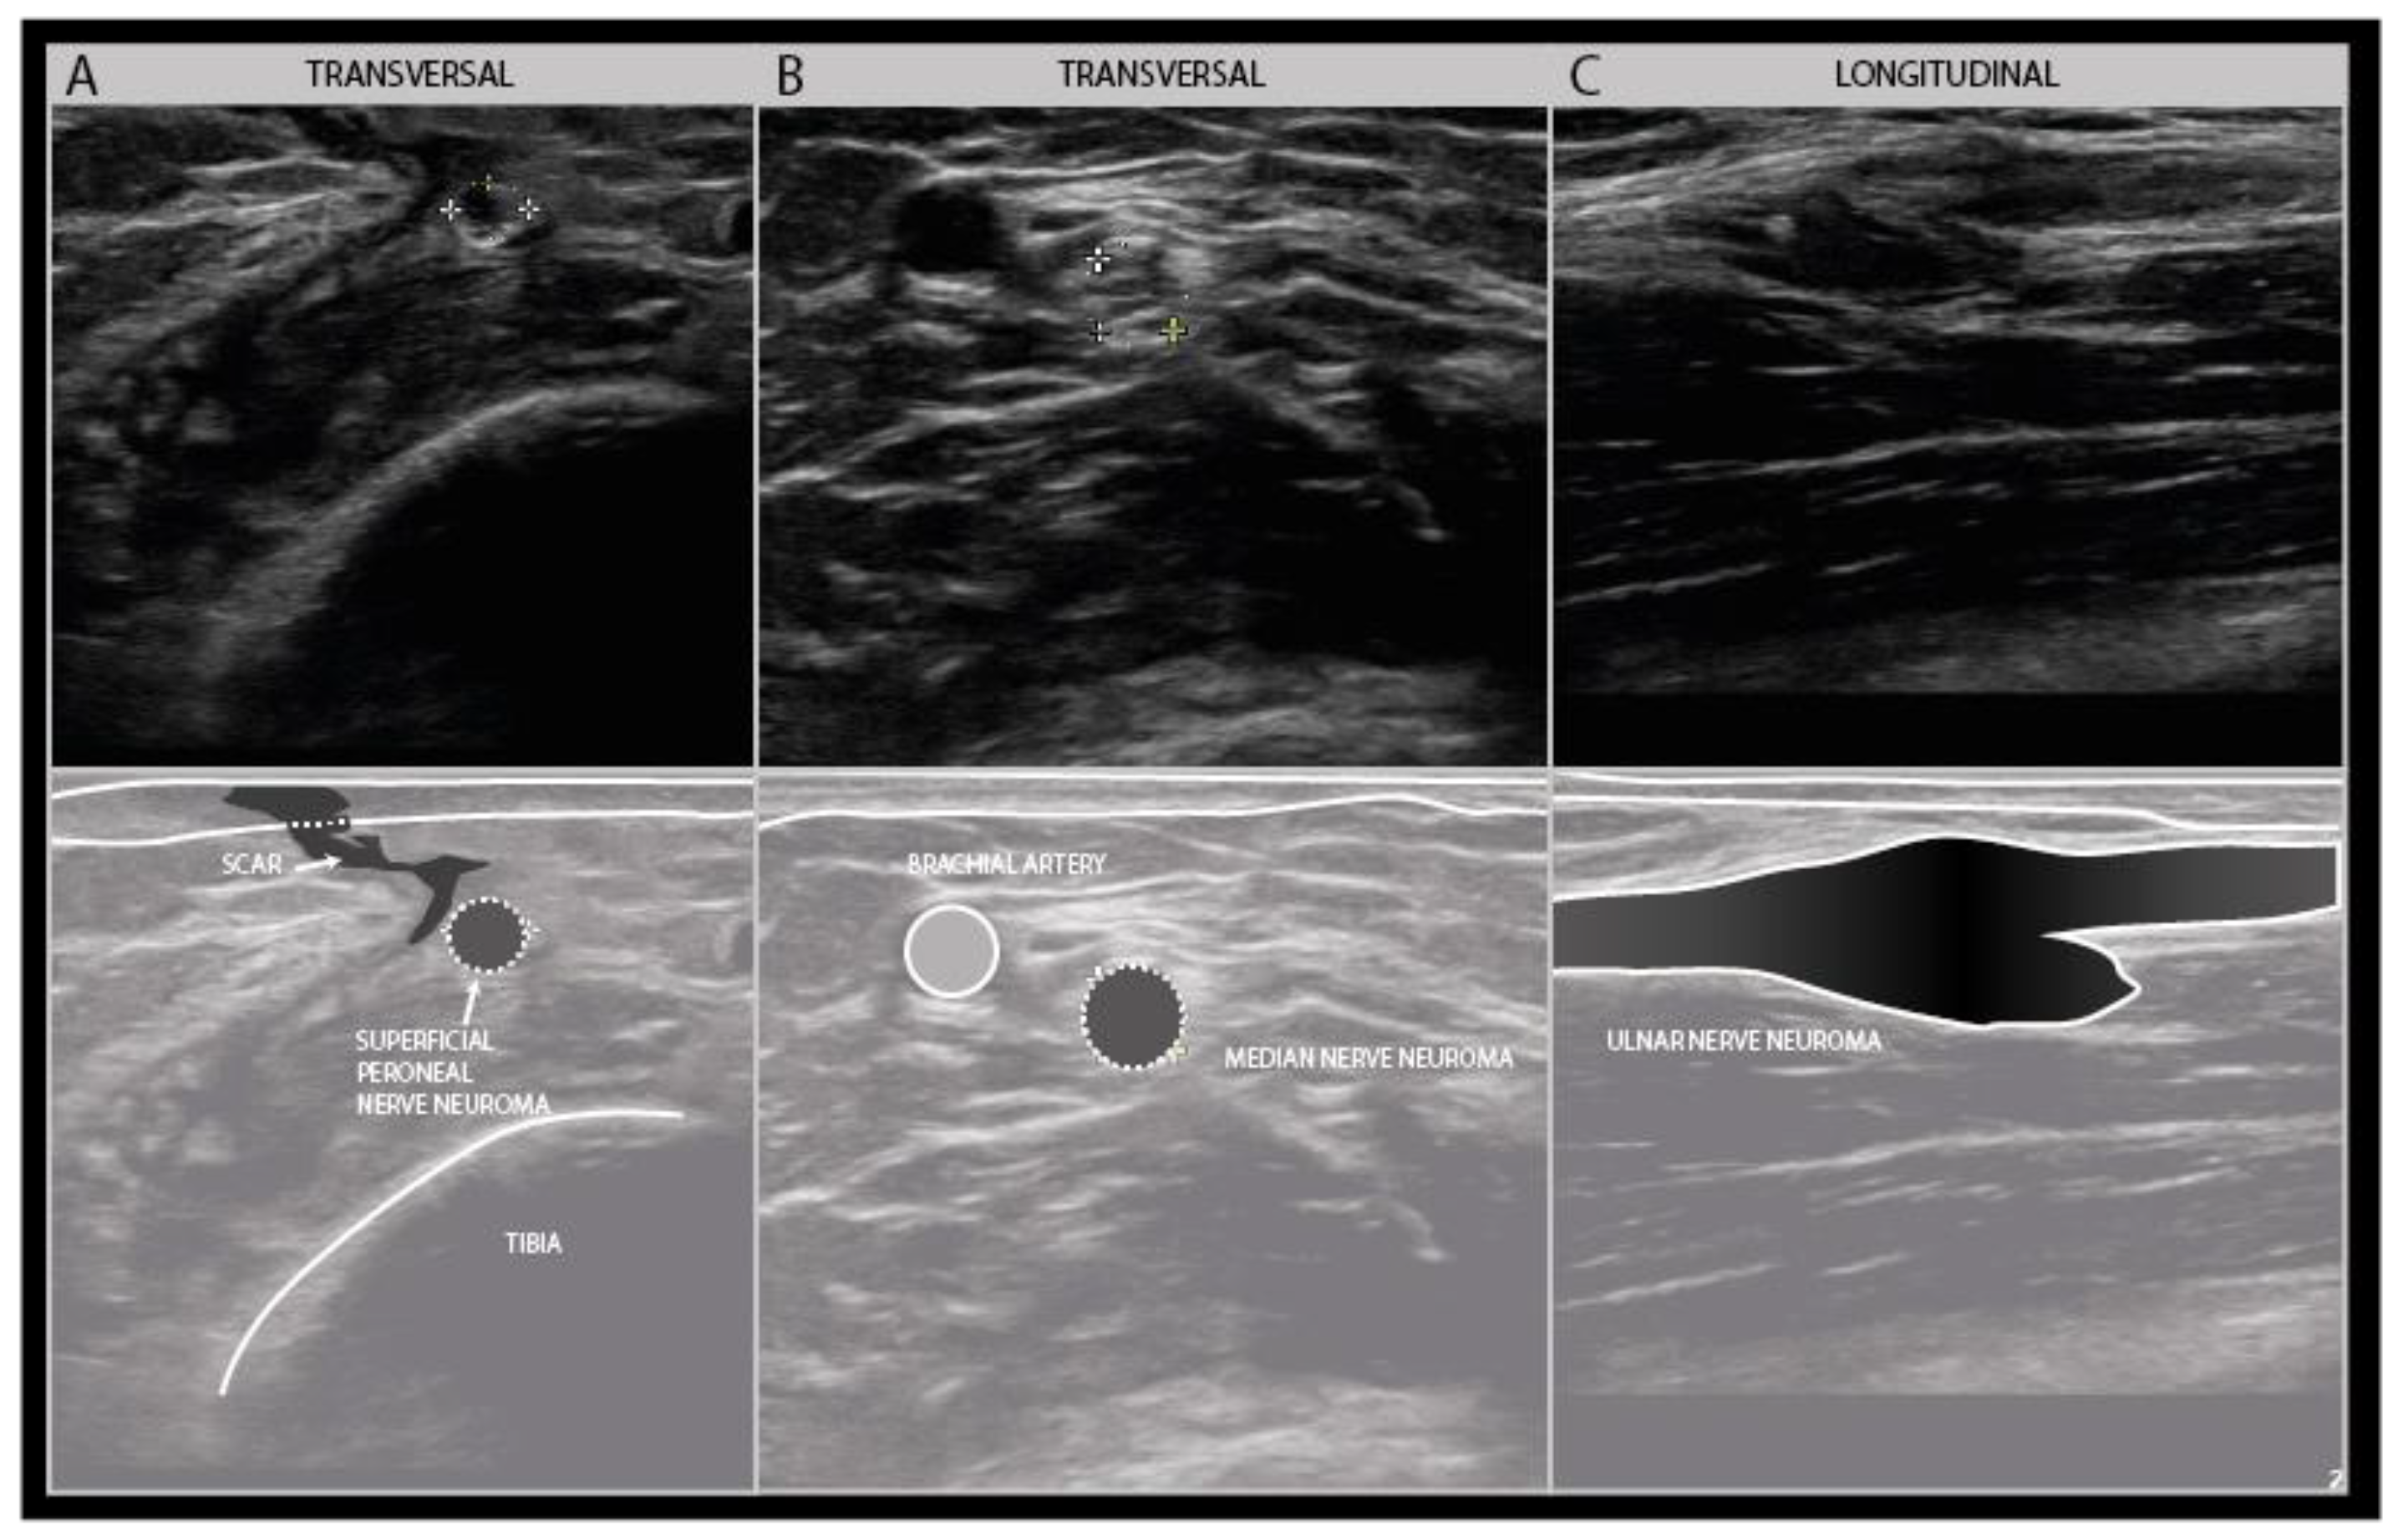

7. Neuroma Outgrowth and Remodeling during Recovery

Depending on the extent of the connective tissue trauma, nerve recovery will give rise to changes in the shape and size of the nerve under study. A traumatic neuroma represents a disordered, hyperplastic growth response to nerve injury, that can give an increase in nerve size from 125 to 1600% of its normal size in the first 1–2 months following the injury [45] (Figure 14).

Examples of traumatic neuroma in continuity. Transverse view of a small superficial peroneal nerve neuroma following a motorbike injury (A). Transverse view of a median nerve traction neuroma from a distal elbow injury (B). Longitudinal view of a large disorganized ulnar neuroma from grenade shard injury to the forerarm (C).